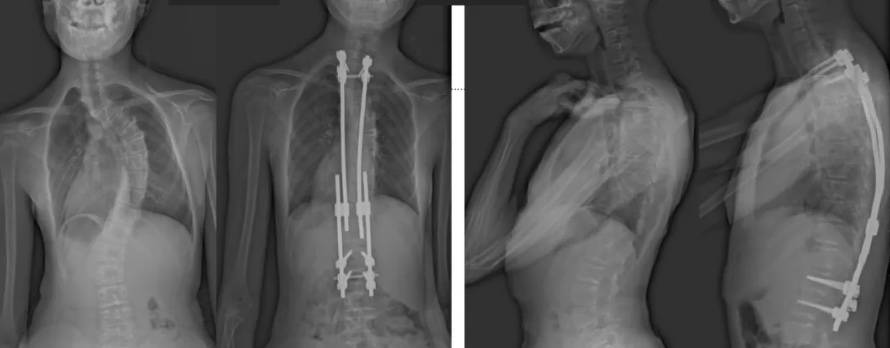

白瑪?shù)恼恍g(shù)前、術(shù)后對比圖(左側(cè));側(cè)位術(shù)前、術(shù)后對比圖(右側(cè))

術(shù)后第二天,白瑪就下地活動了。媽媽驚喜地發(fā)現(xiàn),白瑪一下子“長高”了近十厘米,重新抬起了頭,挺直了脊梁,肩膀也不歪了,可謂“脫胎換骨”。媽媽激動地錄制了一段白瑪走路的身影,把喜悅分享給全家。白瑪?shù)男g(shù)后檢查也提示,手術(shù)成功,恢復良好。